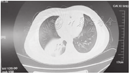

2组患儿病程中均有咳嗽、咳痰等呼吸道症状,均以"肺炎"为入院诊断,塑型组在病程中有发热、行支气管镜前病程≥10 d、镜前热程≥10 d均高于非塑型组(表1),且病程中有发热、镜前热程≥10 d的差异有统计学意义(P<0.05)。塑型组患儿存在气促、呼吸困难,诊断呼吸衰竭者,考虑与树枝样痰栓堵塞支气管、造成肺不张/实变影响通气有关(图1、图2)。

1例7岁女性患儿,入院前后予阿奇霉素联合头孢类抗生素抗感染、糖皮质激素抗炎治疗12 d后,仍有反复发热、复查影像学检查提示炎症吸收不明显,行支气管镜辅助治疗,镜下见塑型,在抗感染同时予2次灌洗治疗,体温正常,复查胸片较前改善。

2组患儿的X线片或胸部CT均提示有大叶性病变,病变分布中塑型组以左下肺最常见(12例,24.0%),非塑型组以右上肺最常见(55例,21.5%),其中塑型组累及双侧者高于非塑型组[4例(8.0%)比20例(7.8%),P=0.883],2组患儿影像学病变分布差异无统计学意义,塑型组合并胸腔积液者高于非塑型组[16例(32.0%)比49例(19.1%),χ2=4.844、P=0.028]。合并肺不张者2组间差异无统计学意义[4例(8.0%)比20例(7.8%),χ2=7.075、P=0.883]。

2组患儿镜下均可见黏膜充血、黏膜水肿,塑型组患儿纤维支气管镜下均可见痰栓堵塞呼吸道(图3),堵塞部位以左下肺多见,与肺部影像学炎症多发部位一致。塑型组有更高比例的黏膜坏死[5例(10.0%)比6例(2.3%),χ2=7.075、P=0.008]。